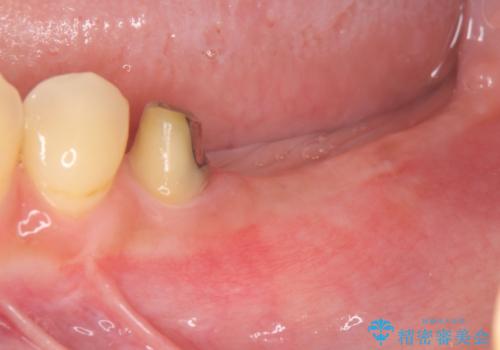

- 他院で根の治療まで終え、違和感が取れず相談に来院されました。

当該歯を精査したところ、歯根に破折が見られ抜歯を余儀なくされました。